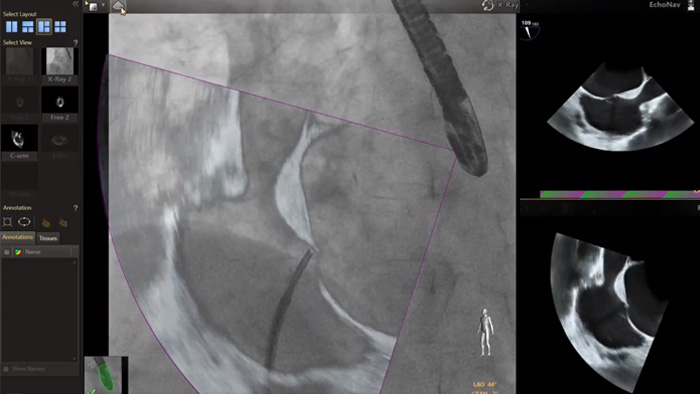

En el centro de nuestra suite, la exclusiva solución EchoNavigator es el ejemplo emblemático del compromiso de Philips con la multimodalidad y la integración del flujo de trabajo, aporta lo mejor de ambos mundos del líder de la industria en soluciones cardíacas intervencionistas de rayos X y ecografía.

Guía de punción transeptal mediante EchoNavigator

Optimización de la vista de la válvula mitral con modelos de corazón EchoNavigator

Optimización de la vista de la válvula tricúspide con modelos de corazón EchoNavigator

Visualización de las válvulas mitral y aórtica con modelos cardíacos EchoNavigator